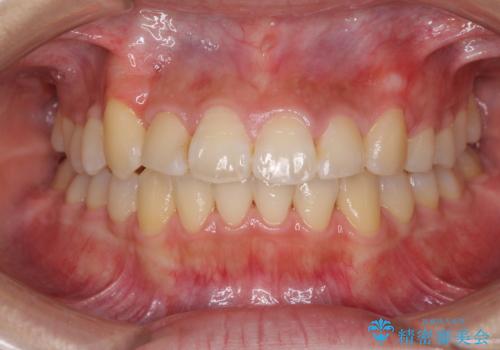

治療の度に歯列が改善していったため、長期間の治療も楽しく過ごしていいただき、満足のいく仕上がりとなりました。

犬歯は歯根が太く長いため、移動には時間を要します。しかし、犬歯は機能面から考えて残すことを選択したいため、長期間をかけて治療を行うこととしました。